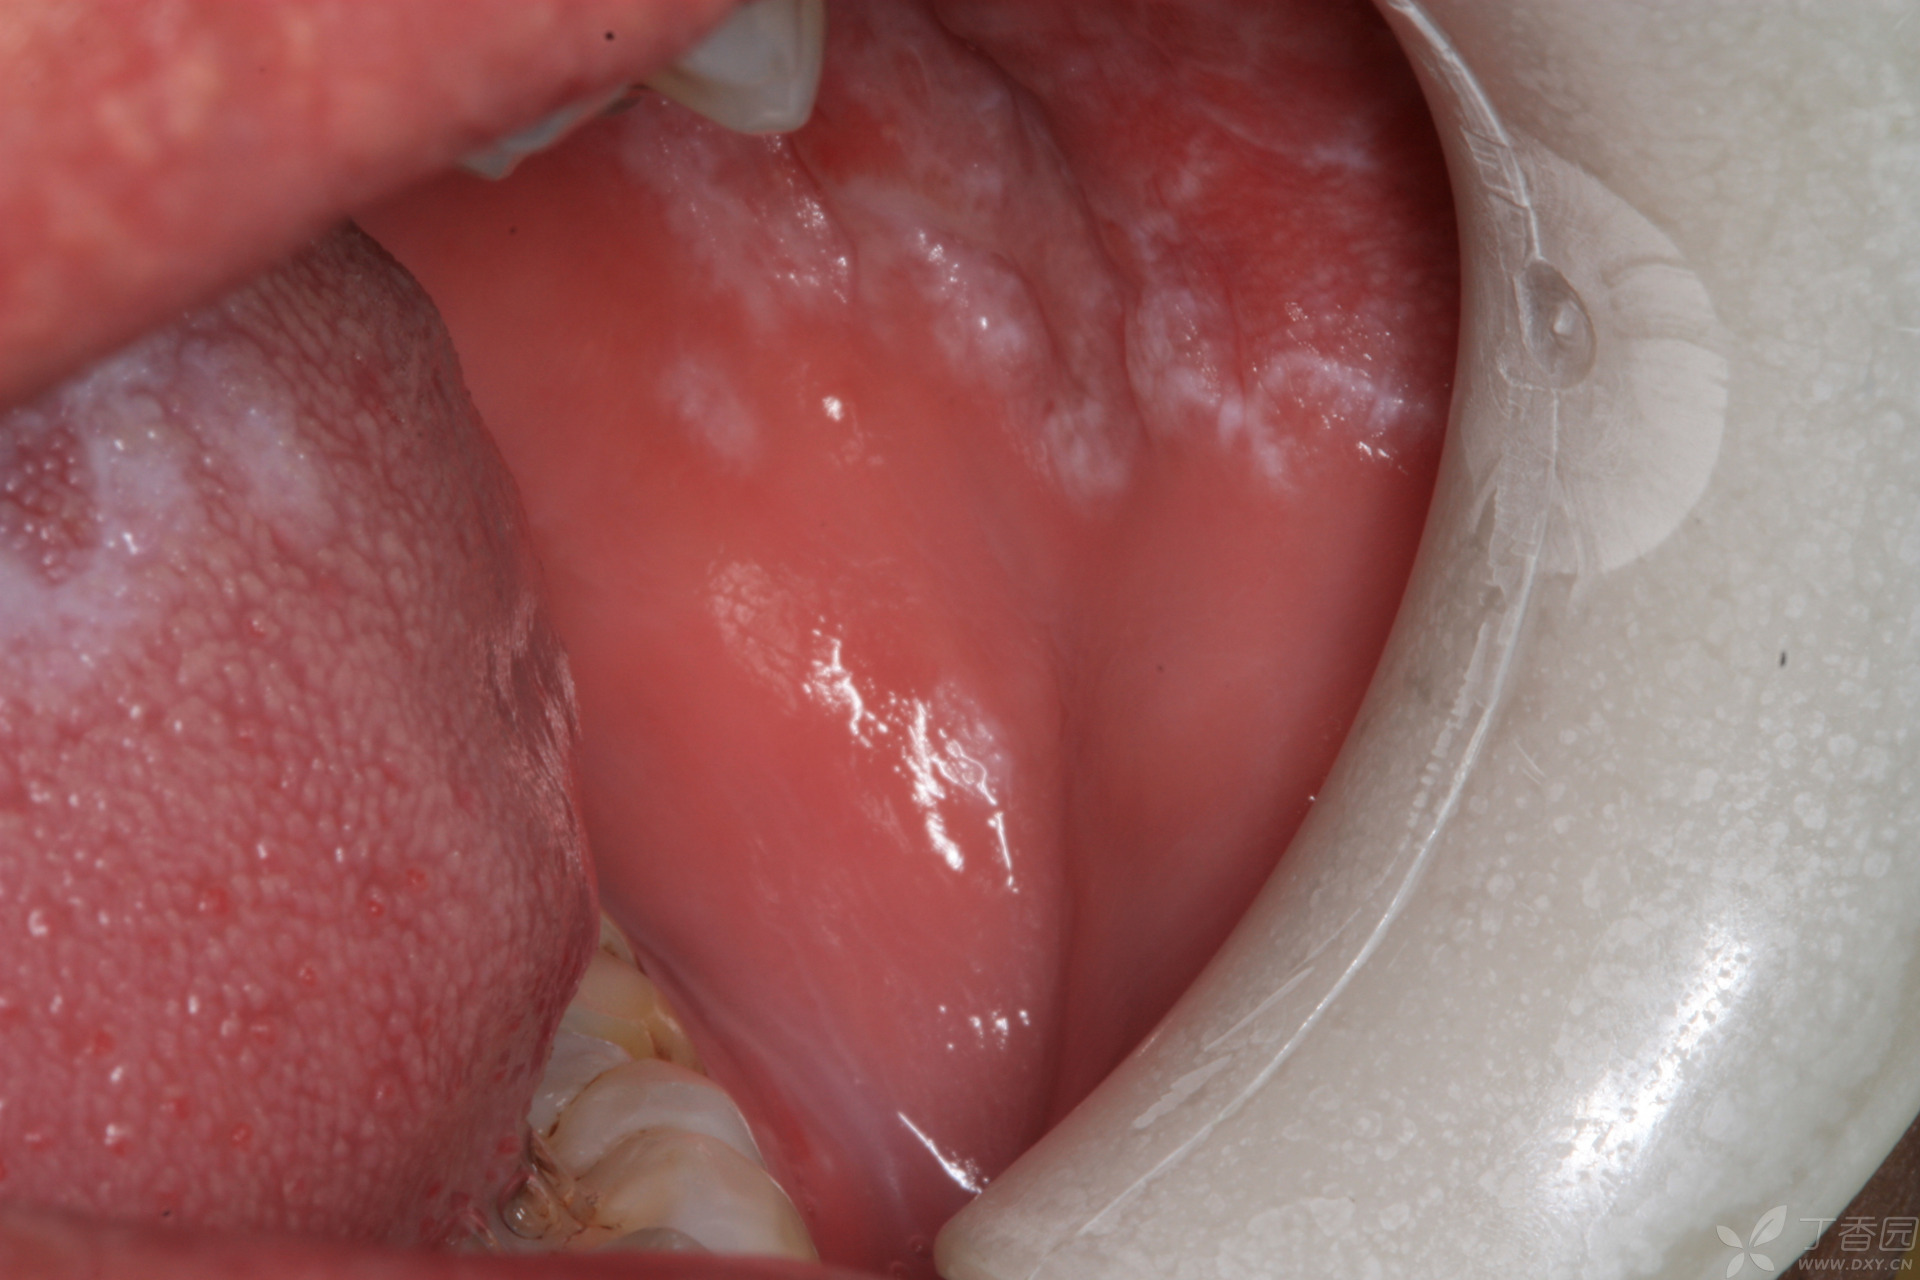

请教各位大神 这是什么粘膜病 - 口腔 -丁香园论坛

图片尺寸4608x3456